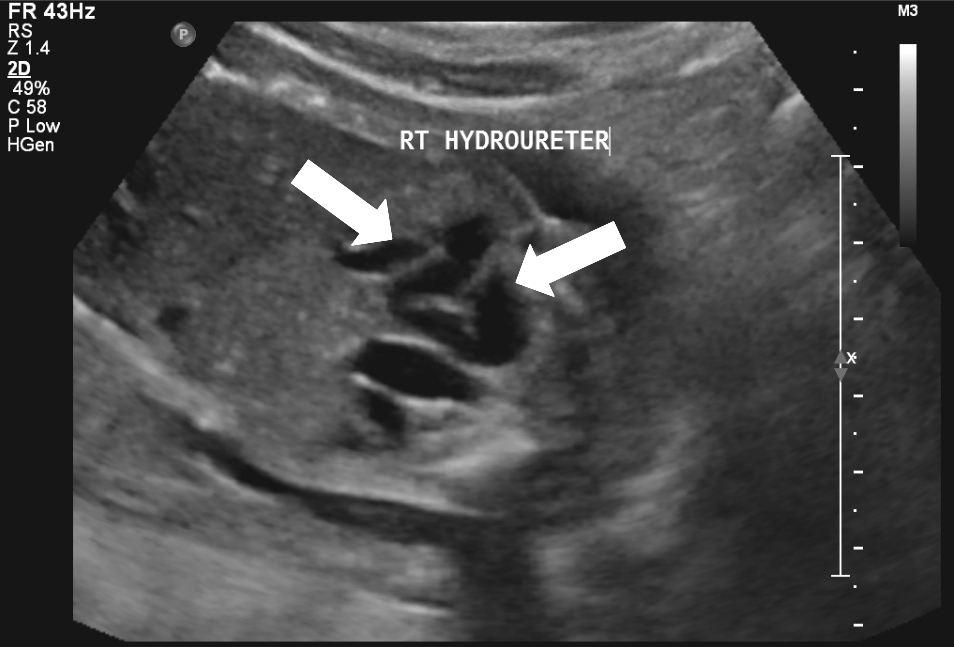

20 weken echografie: links: dikwandige blaas met verwijding van de plasbuis tot aan de kleppen (pijl): het “sleutelgat teken”. Onder: verwijde urineleiders. Bij kinderen gaan de urineleiders bij verwijding ook erg gekronkeld verlopen.